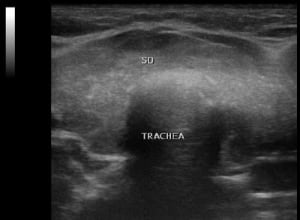

U.a. weisen Gewichtsveränderungen, Zyklusunregelmäßigkeiten und emotionale Instabilität auf Schilddrüsenfunktionsstörungen hin. Derbe Veränderungen in der Schilddrüse hingegen sind verdächtiger als weiche. Zu jeder Schilddrüsenuntersuchung gehört auch der Ultraschall von Schilddrüse und Halsweichteilen (Schilddrüsensonographie). Hierdurch lassen sich Größe und evtl. Veränderungen erkennen sowie relevante Strukturen in der vorderen Halsregion mit beurteilen, insbesondere Nebenschilddrüsen und Lymphknoten. Anhand des Schallmusters und des Durchblutungsmusters (Perfusion) lassen sich häufig bereits Krankheitsbilder festmachen.

So findet sich bei einer Autoimmunhyperthyreose (M. Basedow), einer zumeist schweren Form einer Schilddrüsenüberfunktion, eine ausgeprägte Echoarmut in Verbindung mit einer stark vermehrten Durchblutung des Schilddrüsengewebes. Von den Knoten verdienen solche mit Mikroverkalkungen und einer vermehrten Binnenperfusion verstärkte Aufmerksamkeit.